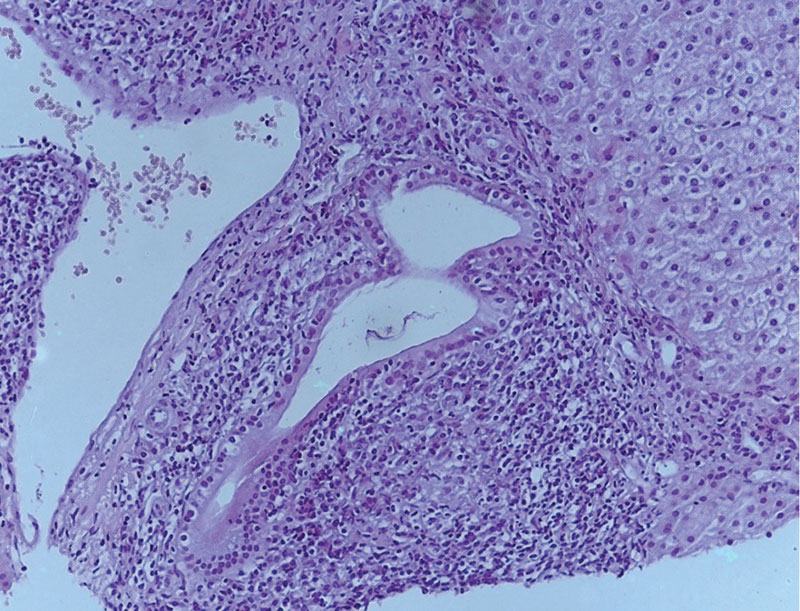

Рис. 1. Портальный и перипортальный гепатит аутоиммунной этиологии. Увеличение × 120

По результатам гистологического исследования биоптата печени были выявлены как характерные черты ПБХ (деструкция мелких желчных протоков), так и признаки АИГ (ступенчатые некрозы, эмпериополез и лимфоцитарные розетки); заключение морфолога: «Аутоиммунный гепатит умеренной степени активности. Первичный билиарный холангит». Стадия фиброза соответствовала F2 по шкале METAVIR. Индекс гистологической активности (ИГА) по Knodell – 9. Морфологическая картина ткани печени представлена на рис. 1 и 2.